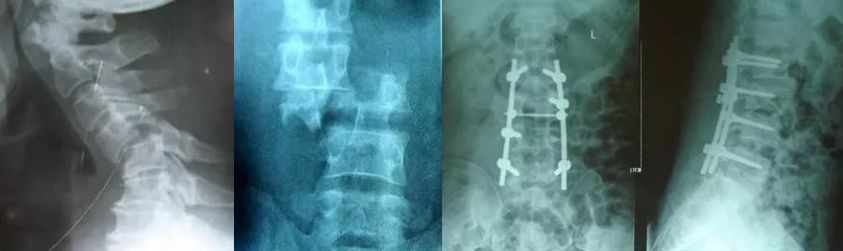

1)脊柱骨折/脱位

• 生命体征平稳,骨折移位较大,有神经症状,应紧急手术;

• 最迟1周之内。

图片